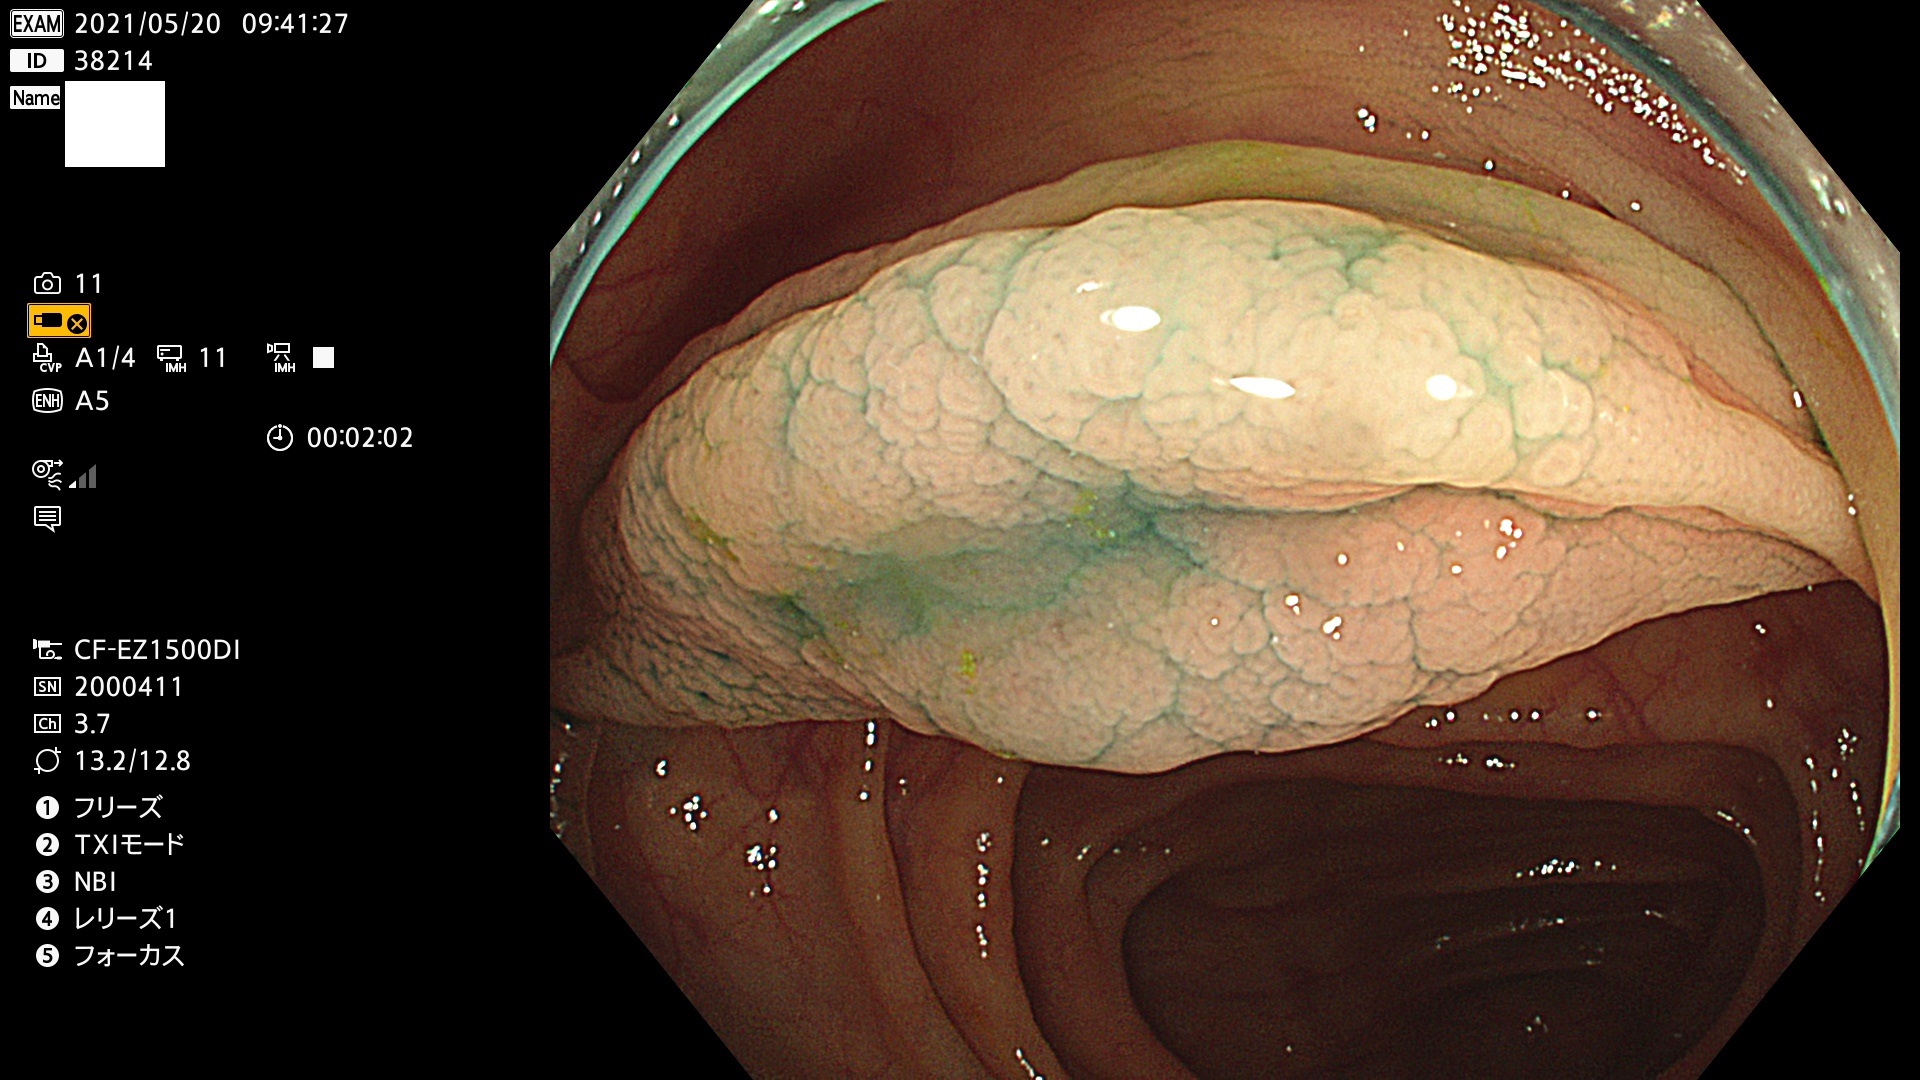

発見困難で危険性の高い平坦型病変(上記100名より抽出)